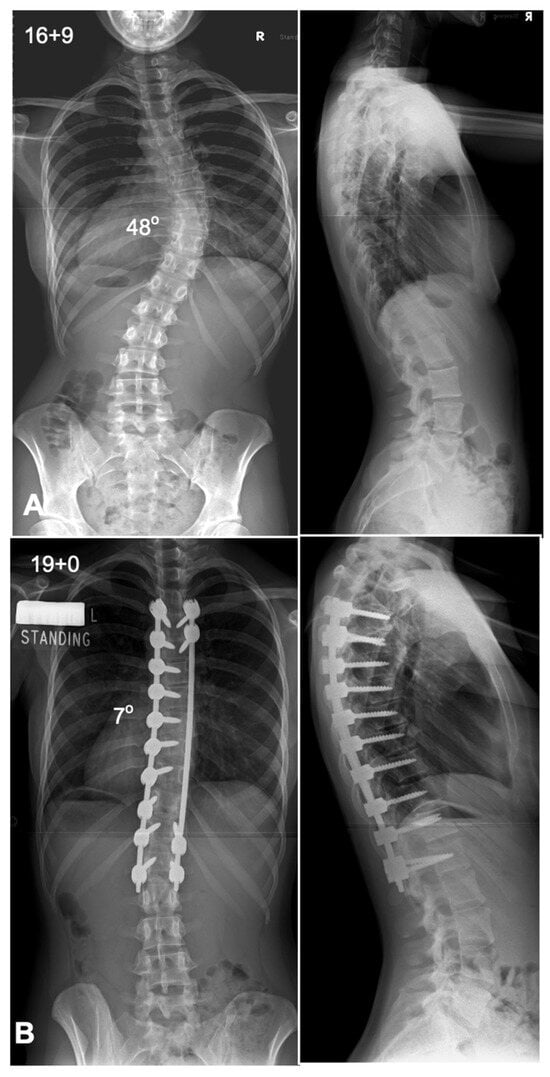

7. Anterior Versus Posterior Fusion in Lenke Type 5 Curves

Lenke 5 AIS, characterized by a primary thoracolumbar/lumbar [TL/L] curve with a compensatory thoracic curve, can be managed with either anterior spinal fusion [ASF] (Figure 6) or posterior spinal fusion [PSF] (Figure 7). The key argument favoring ASF is that it allows for shorter fusion constructs, potentially preserving an additional distal motion segment, which may reduce the risk of low back pain in later life if the fusion can be stopped at L3 rather than L4 [16]. Several studies have compared these approaches, showing that ASF achieves comparable coronal correction with fewer fused segments [17]. However, PSF, facilitated by modern segmental pedicle screw constructs, has become the standard approach due to its technical familiarity and ability to provide superior three-dimensional correction, particularly in terms of lumbar lordosis and thoracic kyphosis restoration [11,18]. Previous studies have indicated a greater loss of sagittal plane correction over time after ASF compared to PSF [17]. Additionally, PSF has been associated with better compensatory thoracic curve correction and improved trunk shift realignment [16,17]. Importantly, factors such as curve magnitude, lowest instrumented vertebra angle, and apical vertebra translation influence the decision on how far to extend the fusion distally. A predictive equation has been developed to guide this decision in PSF, helping to determine whether stopping at the Cobb-to-Cobb levels of the curve is sufficient or if additional distal levels should be included, in which case there may be an indication to consider performing an ASF instead [18]. Ultimately, both approaches have their strengths, and the choice should be individualized based on patient anatomy, surgical goals, and the surgeon’s expertise.